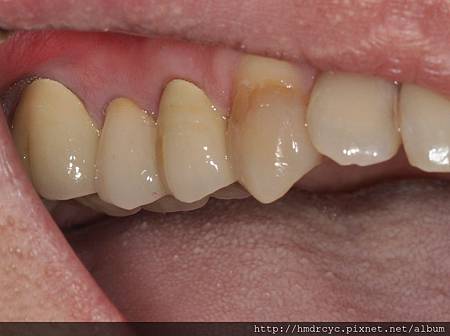

套上假牙套之後牙齒恢復的美觀與耐用度

楠梓的L小姐非常開心

原本斷裂的牙齒竟然救回來